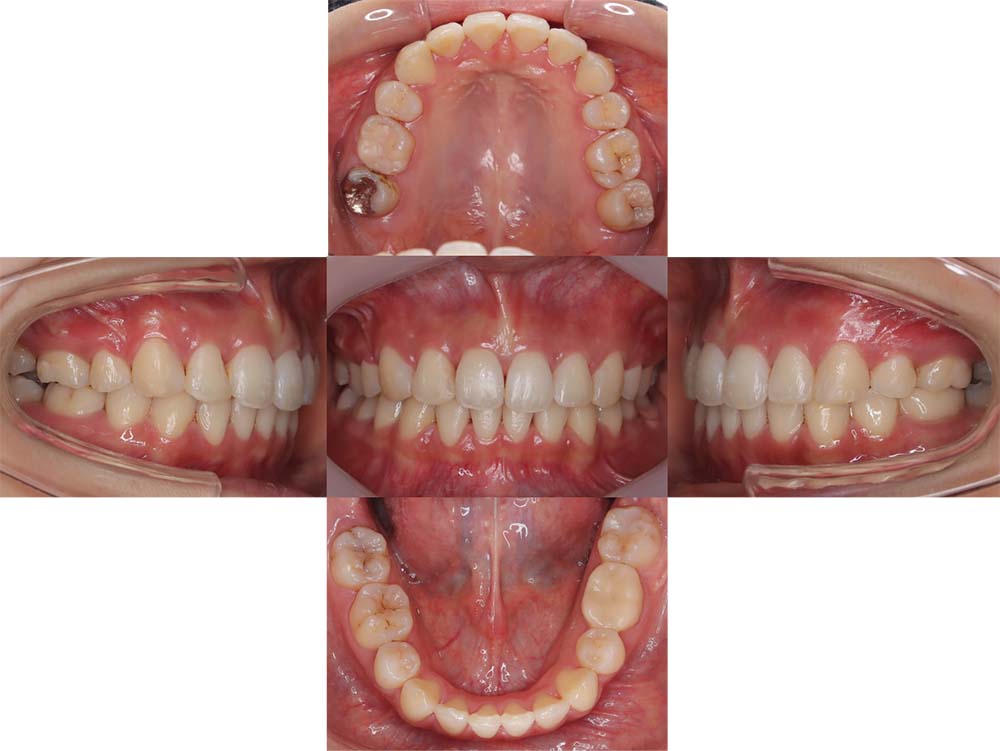

症例03

| 主訴 | 歯並びがガタガタしている。 |

| 診断名あるいは主な症状 | 過蓋咬合、叢生 |

| 年齢/性別 | 26歳・女性 |

| 矯正ステージ | 大人の矯正治療 |

| 治療方法 |

ワイヤー矯正 歯科矯正用アンカースクリュー(3本) |

| 抜歯部位/抜歯有無 | 抜歯 |

| 治療内容 | 上下顎の奥歯を後方に移動後、ガタガタの改善と上下顎前歯を後退させた。 |

| 費用 |

90万円程度(2025.10時点の料金となります。) ※矯正基本料金、アンカースクリュー、審美ブラケットを含む |

| 治療期間 | 2年8ヶ月 |

| 主なリスク・副作用 | 痛み、歯根吸収、歯肉退縮、虫歯、後戻り |